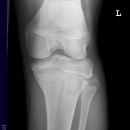

Gonarthrose